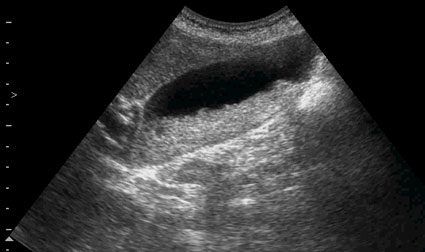

Повторная сонограмма через сутки.

Думаю, что это варианты трансформации коллоидальной устойчивости самой желчи,точнее слажа, т.е.фазовые переходы: фезикулярный агломерат - жидкий кристалл - истинный кристалл и обратно

Разделяю точку зрения высказанную выше. Dynamical US control of GB sludge formation stages.